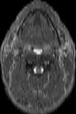

Visible Human male: Sectio transversalis 1210

CT

NMR

Pd T1 T2